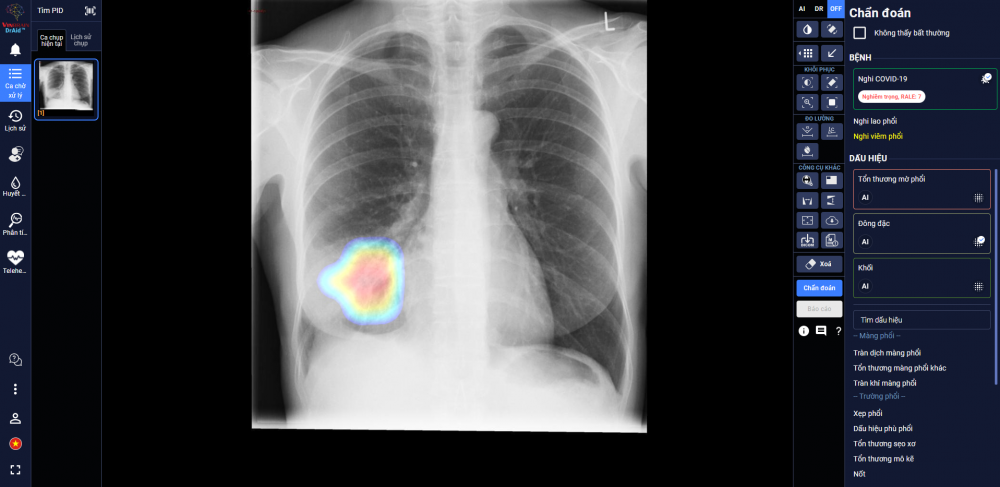

Sản phẩm DrAid cho Covid-19 vừa được Hội đồng Khoa học Bộ Y tế nghiệm thu và kiến nghị nên sớm đưa vào sử dụng tại các bệnh viện trong giai đoạn Covid-19 đang tiếp tục lây lan như hiện nay.

![]() |

| DrAid giúp bác sĩ theo dõi mức độ tổn thương phổi ở một bệnh nhân F0 trên ảnh X-quang phổi. (Nguồn: LĐTĐ) |

Ngày 21/9, Công ty VinBrain (thuộc Tập đoàn Vingroup) công bố chính thức hoàn thiện một sản phẩm công nghệ hiện đại góp phần hữu hiệu trong công tác dự phòng và kiểm soát dịch Covid-19 có tên gọi DrAid cho Covid-19.

Sau hơn 1 năm nghiên cứu và phát triển, đây là sản phẩm ứng dụng trí tuệ nhân tạo (AI) có khả năng đưa ra lời giải toàn diện cho bài toán Covid-19 từ khâu hỗ trợ chẩn đoán tới việc tiên lượng điều trị.

Đến nay, sản phẩm DrAid cho Covid-19 đã tổng hợp được nguồn dữ liệu rất lớn về Covid-19, gồm hơn 21.400 hình ảnh X-quang ngực của bệnh nhân dương tính với SARS-CoV-2 và hơn 118.000 ảnh X-quang ngực tiêu chuẩn.

Hiện tại, sản phẩm DrAid cho Covid-19 hội tụ nhiều ưu điểm nổi bật như chủ động cảnh báo Covid-19 trong mọi tình huống. Khi được tích hợp vào các máy chụp X-quang hoặc hệ thống công nghệ thông tin sẵn có tại các bệnh viện và cơ sở y tế, DrAid cho Covid-19 sẽ hoạt động như một "màng lọc" virus SARS-CoV-2 đầu tiên trên diện rộng, giúp các bệnh viện và cơ sở y tế chủ động phát hiện người nghi nhiễm Covid-19.

Do đó, khi người dân đi kiểm tra sức khỏe được chỉ định chụp X-quang, ngay khi ảnh được đẩy lên hệ thống, DrAid cho Covid-19 sẽ lập tức cảnh báo nếu phát hiện các dấu hiệu nghi nhiễm Covid-19, qua đó giúp các bệnh viện hoặc cơ sở y tế nhanh chóng có phương án cách ly hạn chế lây nhiễm, cũng như kịp thời điều trị cho bệnh nhân.

Tại các khu cách ly tập trung hoặc khu có nguy cơ cao, DrAid cho Covid-19 giúp phân luồng bệnh nhân trước khi xét nghiệm PCR. Các F1 nghi nghiễm được khoanh vùng ngay và làm xét nghiệm PCR mẫu đơn, các trường hợp không nghi nhiễm thì làm PCR mẫu gộp và cách ly bình thường, nhờ vậy giúp tiết kiệm ngân sách Y tế.

Trong các bệnh viện thu dung điều trị Covid-19, DrAid cho Covid-19 giúp các bác sỹ đánh giá mức độ tổn thương phổi của bệnh nhân qua từng ngày, từ đó đưa ra các chỉ định điều trị kịp thời và hiệu quả.

DrAid cho Covid-19 hiện đang được sử dụng để hỗ trợ các bác sĩ tiên lượng điều trị cho bệnh nhân Covid-19 tại một số bệnh viện dã chiến tại TP HCM và Hà Tĩnh.

Giá trị hỗ trợ chẩn đoán và tiên lượng điều trị của DrAid cho Covid-19 cũng đã được chứng minh và sử dụng thực tiễn trên các xe hay máy chụp lưu động với liều tia X-quang chỉ bằng 1/4 máy chụp X-quang trước đây.